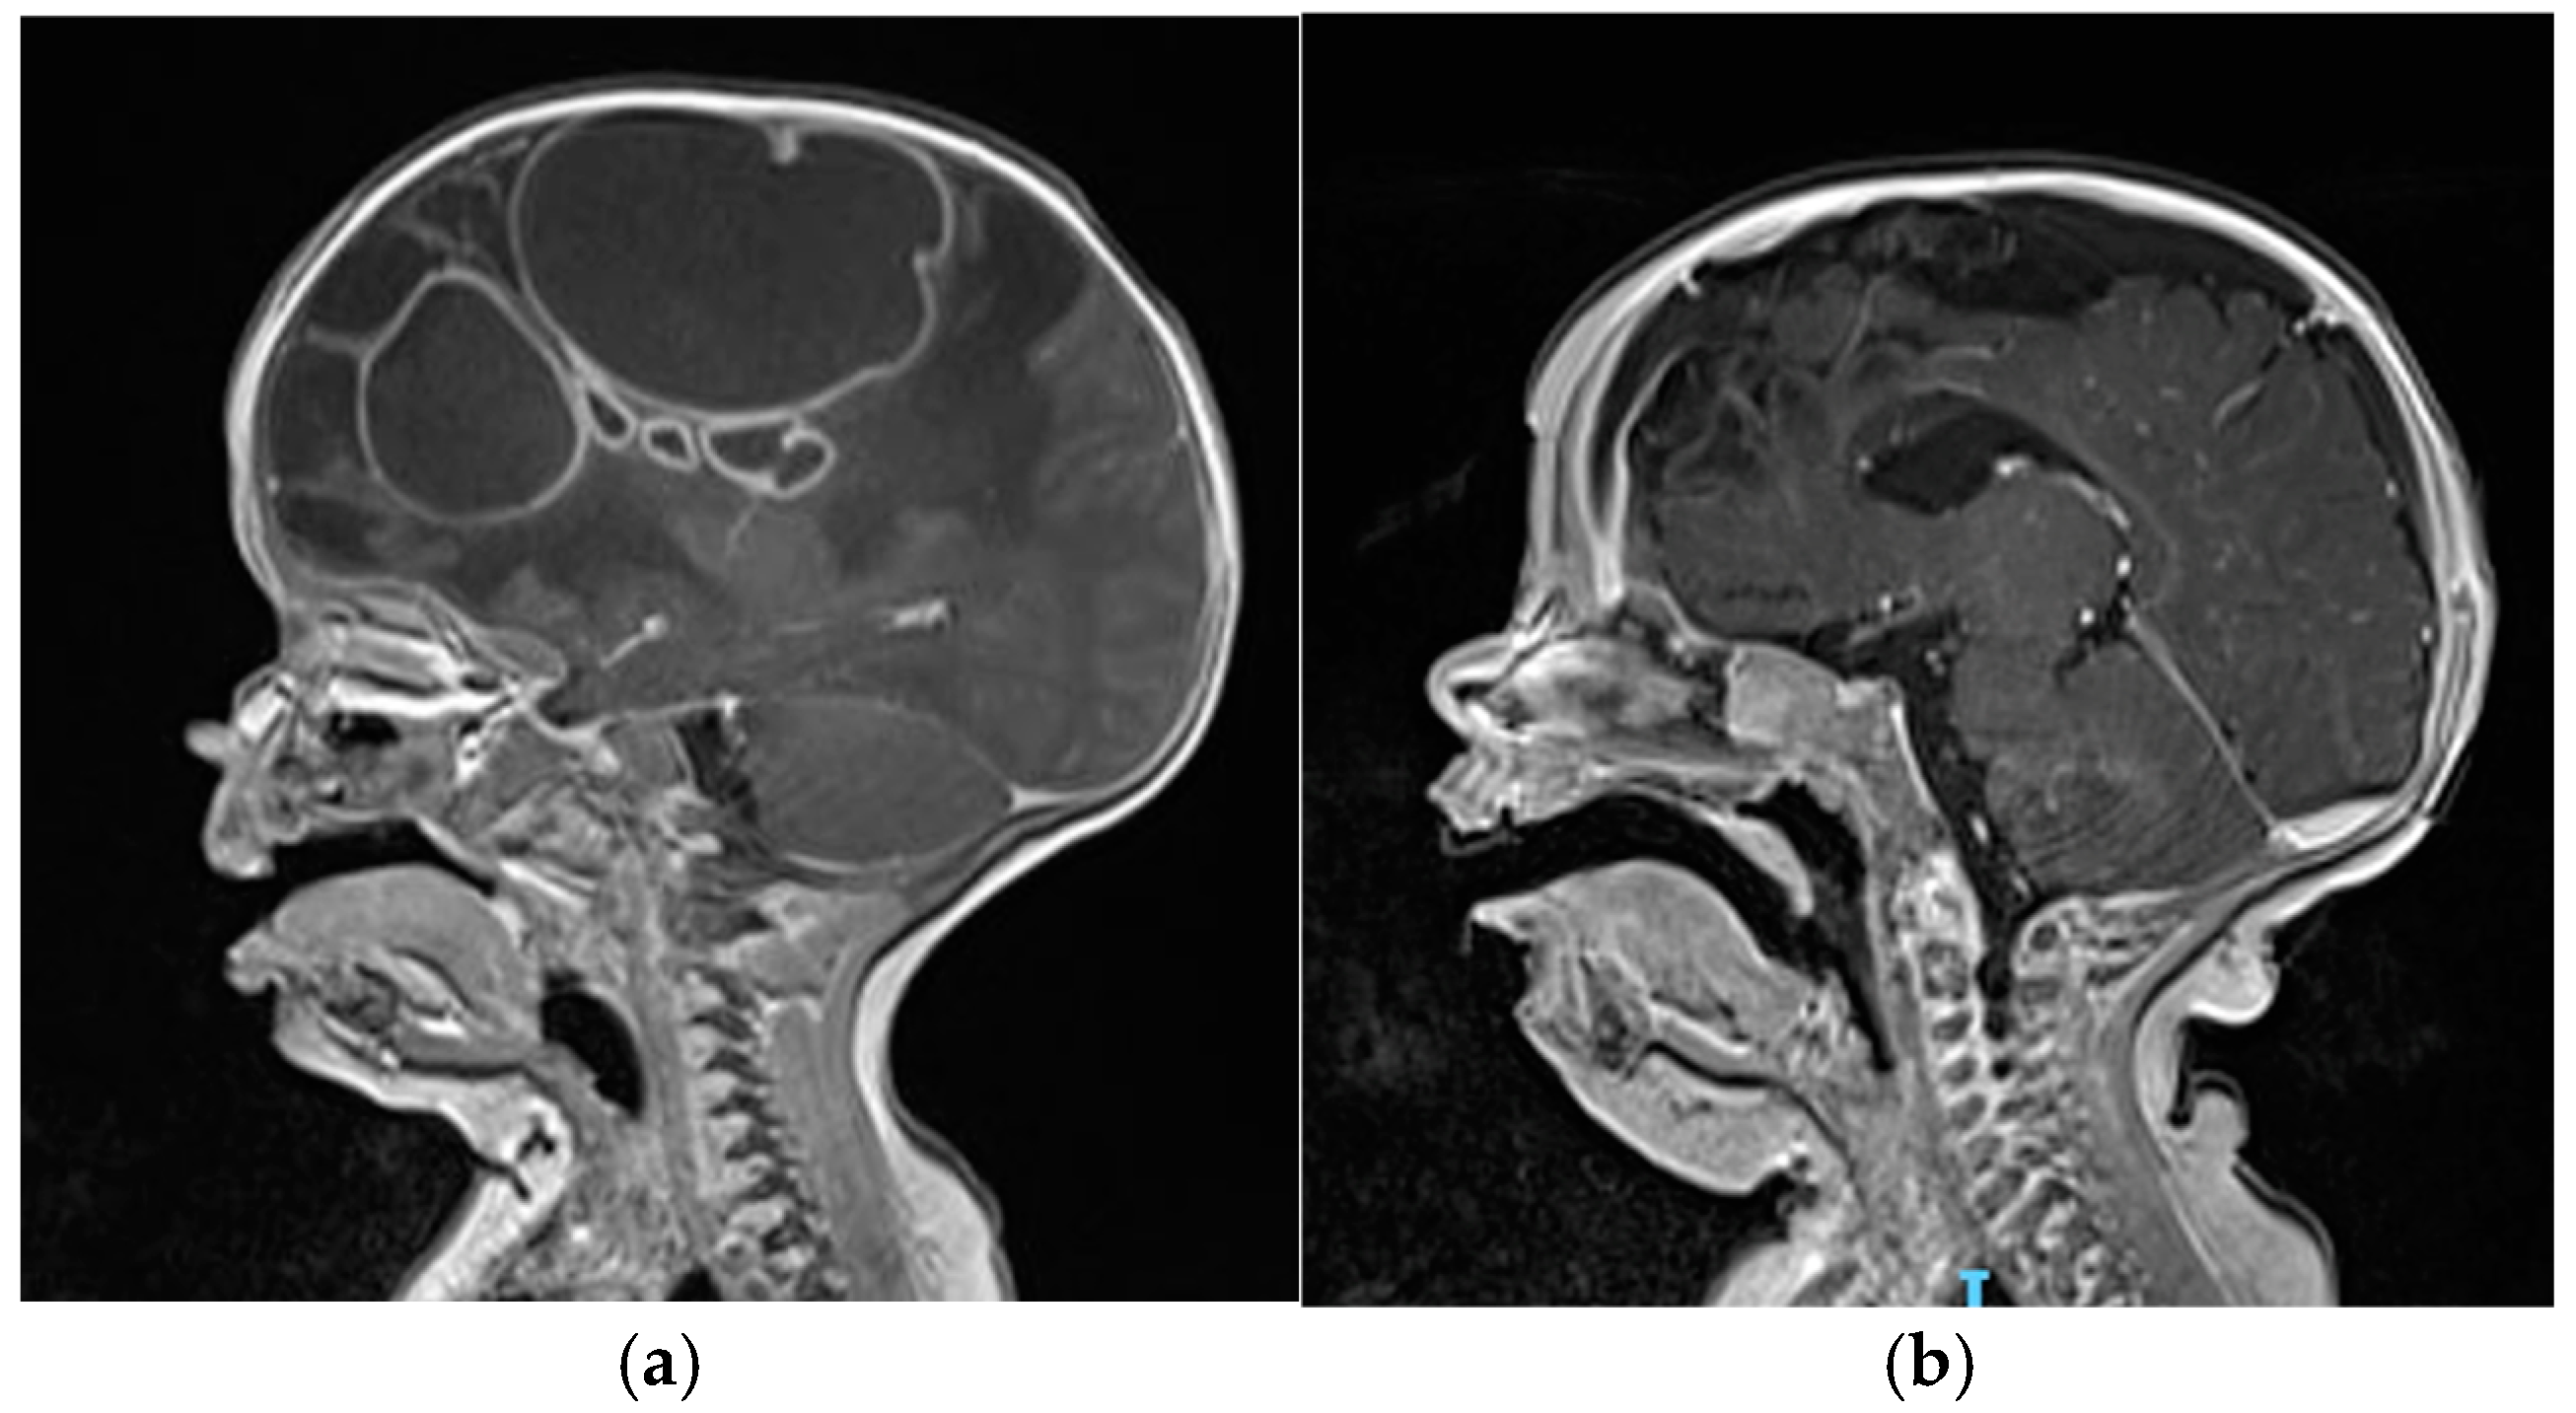

3. Detailed Case Description